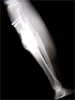

Progress

Correction in 2 planes with translation

Good correction with lateral hump to maximise cosmetic result